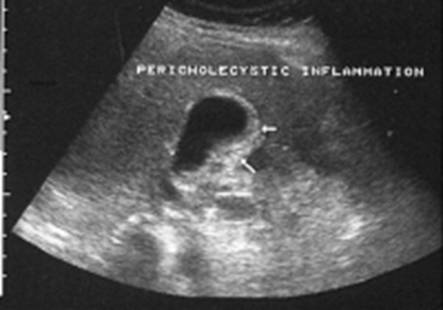

Fig 3 Esame ultrasonografico dell'addome . slaminamento della parete colecistica

Fig 4 Esame ultrasonografico dell'addome . slaminamento della parete colecistica